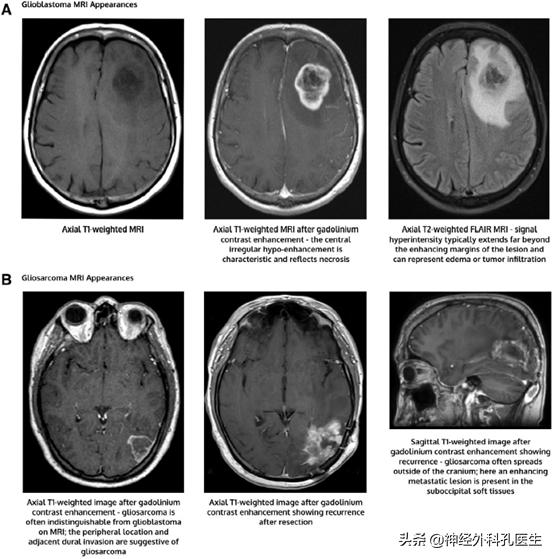

在组织学上,这两种类型的胶质母细胞瘤的特征仍然是高级别星形细胞瘤,其中包含微血管增生区域和/或局灶性坏死(图1)。

然而,在IDH野生型胶质母细胞瘤中,也存在一些特定的组织学变异。巨细胞胶质母细胞瘤包含大的、高度多形性的、多裂的巨细胞。胶质肉瘤呈交替区域,具有恶性星形细胞特征和肉瘤样间质上皮化生。最后,上皮样胶质母细胞瘤是一种新的变异,其特征是肿瘤细胞具有明显的上皮样形态。这种变异值得注意的是,携带BRAF V600E突变的比例很高(约一半)。然而,目前的治疗建议并不因组织学的不同而不同。胶质母细胞瘤和胶质肉瘤的特征性MRI表现如图1所示。巨细胞胶质母细胞瘤或上皮样胶质母细胞瘤的影像学特征不能可靠地区分这些肿瘤。